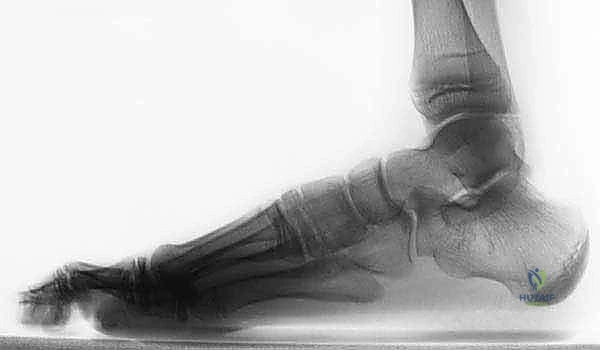

- الأشعة السينية التقليدية (X-Rays): يتم أخذ صور بوضعيات خاصة (مثل وضعية Harris-Beath) لرؤية المفصل تحت الكاحل. قد تظهر الأشعة السينية الائتلاف العظمي بوضوح، بالإضافة إلى علامات ثانوية مثل "علامة حرف C" (C-sign) التي تدل على تشوه في عظم الكاحل، أو وجود نتوءات عظمية (Osteophytes) تشير إلى بداية خشونة المفاصل المجاورة.

- التصوير المقطعي المحوسب (CT Scan): يُعد المعيار الذهبي (Gold Standard) لتشخيص ائتلاف الكاحل العقبي. يطلب الدكتور هطيف إجراء أشعة مقطعية ثلاثية الأبعاد، حيث توفر صوراً متناهية الدقة للتركيب العظمي، تحدد حجم الائتلاف، موقعه الدقيق، ونسبة إصابة المفصل. هذه الخطوة حاسمة جداً قبل اتخاذ قرار الجراحة.